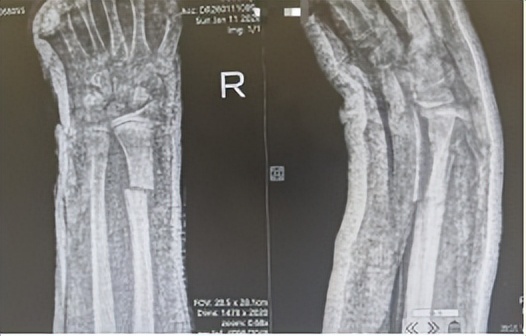

阳光讯(记者 郑亚雷 通讯员 曾雪琴)1月11日,小婕在玩耍时不慎摔倒,右手腕着地后受到强烈冲击,当即出现剧烈疼痛,手腕迅速肿胀且活动受限。家长焦急万分,立即带其前往西安市红会医院手法复位室就诊。经过影像学检查和详细查体,小婕被确诊为右尺桡骨骨折,在科主任董博及副主任医师周健的指导下,来晓宇主治医师为其实施了精准闭合手法复位。目前,患儿病情稳定,恢复良好。

董博主任表示,尺桡骨骨折是儿童常见的骨折类型。若处理不当,可能影响骨骼的正常发育及未来腕关节功能。小婕的尺骨与桡骨骨折线不在同一平面,且尺骨移位明显,复位难度较大。考虑到小婕年龄较小,为最大限度减少创伤、保护骨骼正常发育。董博主任、周健副主任医师与来晓宇主治医师经过充分评估,最终决定采用闭合手法复位联合石膏外固定的保守治疗方案。

在复位过程中,董博主任与周健副主任医师全程指导,来晓宇主治医师凭借丰富的临床经验,精准把控复位的力度与角度,顺利完成了闭合复位操作。术后影像显示,骨折断端对位对线良好,达到理想复位效果。来医生还向家属详细讲解了石膏固定期间的护理要点、患肢功能锻炼方法及后续复查安排。